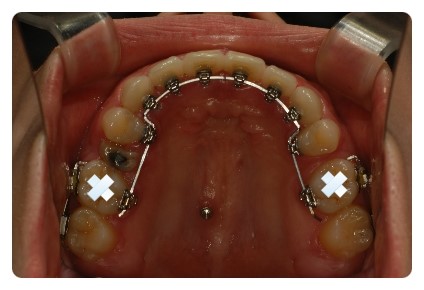

상하악 발치상태나 공간이 다름에도 불구하고

중심선이 크게 어긋나지않게 맞춰가면서 천천히 진행중이에요

거의 다 닫혀가는 상악 !!

입천장 와이어랑 고무줄도 떼엇어요

맞다 저 브라켓 탈락 상습범이엇던거 아시죠 ㅠㅠ

진짜 신기한건 저렇게 양옆으로 붙인뒤로는 단한번도 안떨어지는중 ~~~